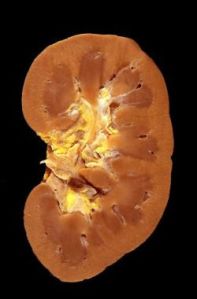

First, a normal kidney looks like this:

This is normal. It sort of looks like a bean, right? Nothing looks particularly gross or wrong. Normal.